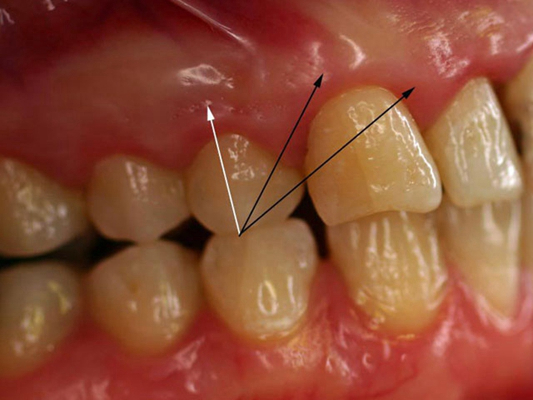

牙齦炎圖片

牙齦炎和牙周炎